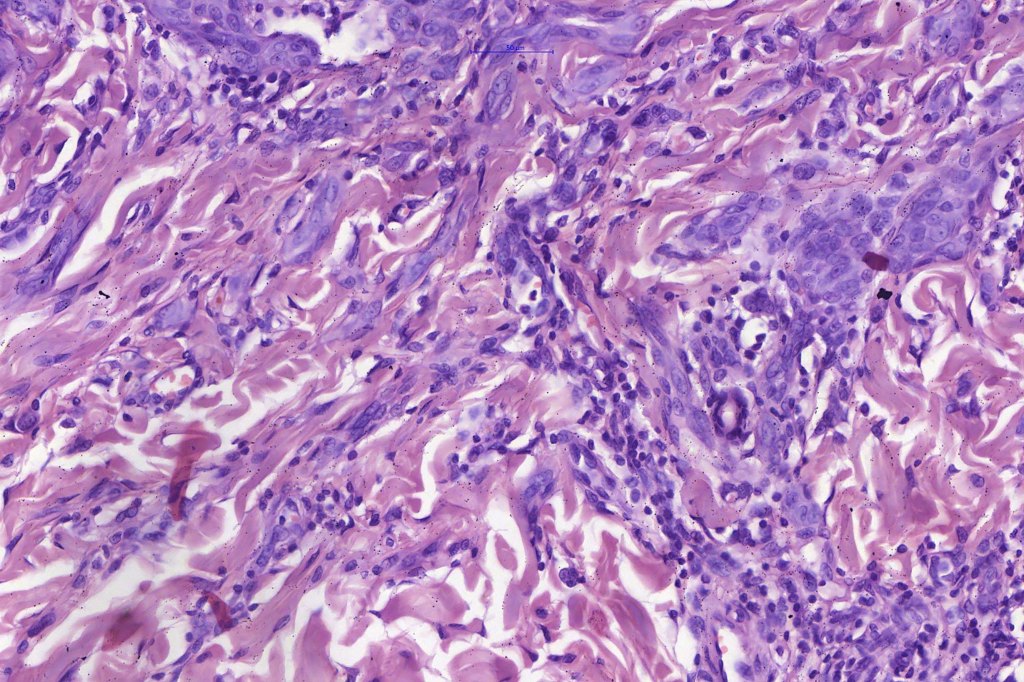

•Spindle cell nests often display a “raining down” growth pattern

•Spindle cells have abundant cytoplasm and vesicular nuclei with small nucleoli

•Epithelioid cell variants often show greater pleomorphism and cells can frequently appear bizarre with abundant, sometimes ground glass cytoplasm and large vesicular nuclei with prominent eosinophilic nucleoli, multinucleate cells are often seen

•Lymphocytic infiltration at the base of the lesion